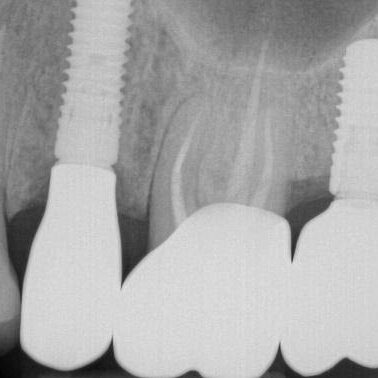

ULTRASONICS: Complications of Abutment Screw Retrieval Secondary to Prior Ultrasonic Attempts

There has been much written on the use of ultrasonics in retrieving fractured screw fragments, which I didn’t think a lot about until May of 2023, as it has not been a part of my fractured screw retrieval algorithm.